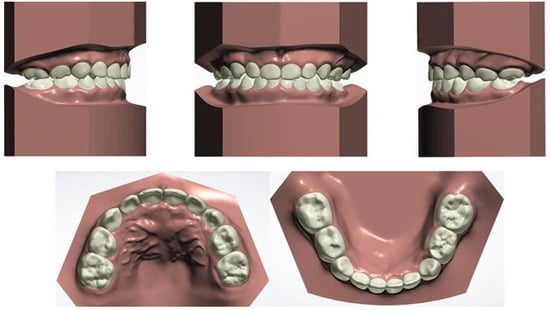

3. Results

A total of 28 aligners were used during the whole treatment period. A healthy occlusal relationship, improved dental esthetics and a better lateral profile were eventually obtained. Following the narrowing of the upper dental arch and enlargement of the lower dental arch, the maxillary and mandibular widths were matched. Mild mandibular molar distalization and maxillary molar mesialization were used to acquire an ideal canine and molar sagittal relationship by correcting the bilateral posterior scissor bite and anterior crossbite. By adjusting the angle of the incisors, we achieved the optimal overbite and overjet for the patient. Esthetic improvement and a relatively straight profile were also achieved due to his labially inclined upper incisors from the lateral view (Figure 17). Figure 18 depicts the initial and final lateral cephalograms. No recurrence of the anterior crossbite or bilateral posterior scissor bite was observed during the 3-month follow-up.

The data of treatment outcomes are displayed in Table 2, with regard to dental arch widths, basal skeletal widths, palatal volume and surface area. In contrast with the initial and final model in Figure 19, mandibular arch narrowing following maxillary and arch expansion was achieved by Invisalign aligners. Moreover, the intricate relationships between a 3-year-old boy’s malocclusion, airway and the rest of his body were of significant interest. Pediatricians, otorhinolaryngologists, orthodontists and other professionals have long been interested in the association between respiratory patterns and facial skeletal development [18,19].

Figure 19. Initial and final model overlay contrast.